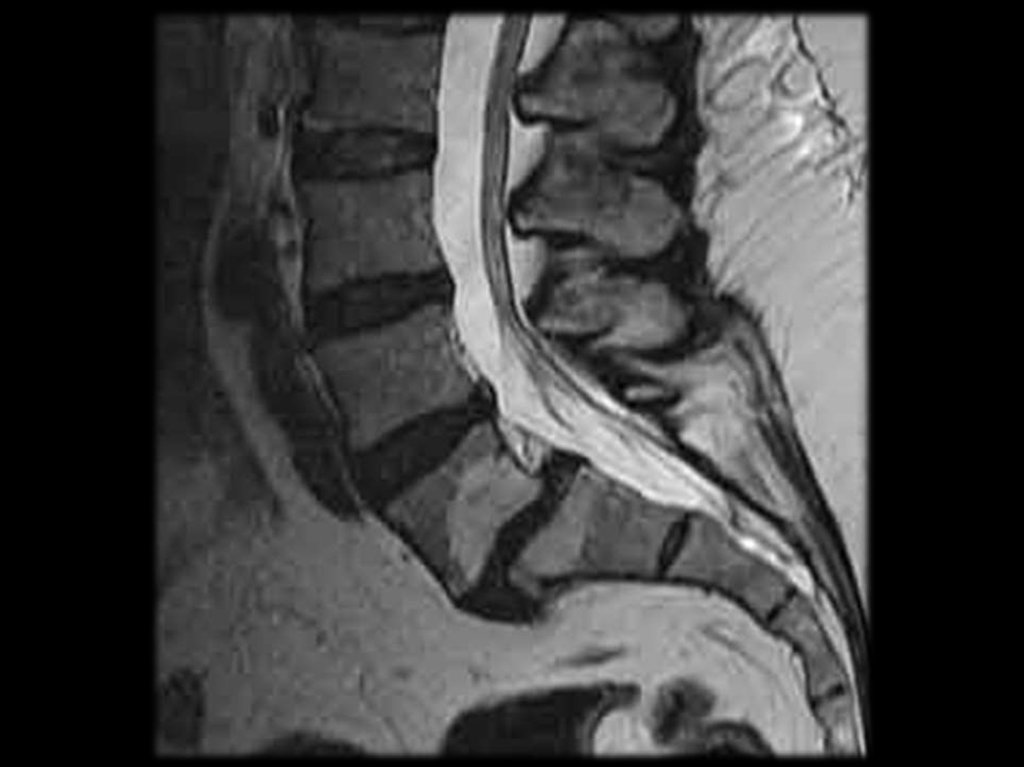

На поясничном уровне наиболее значимы

протрузии и грыжи дисков, а также патология

межпозвонковых суставов.

Грыжа диска

Грыжа диска – выпячивание диска за края линии,

соединяющей тела позвонков более 3 мм.

Выпячивание

диска

считается

клинически

значимым, если выпячивание занимает больше

25%

переднезаднего

размера

диаметра

позвоночного канала (≈ 10 мм).